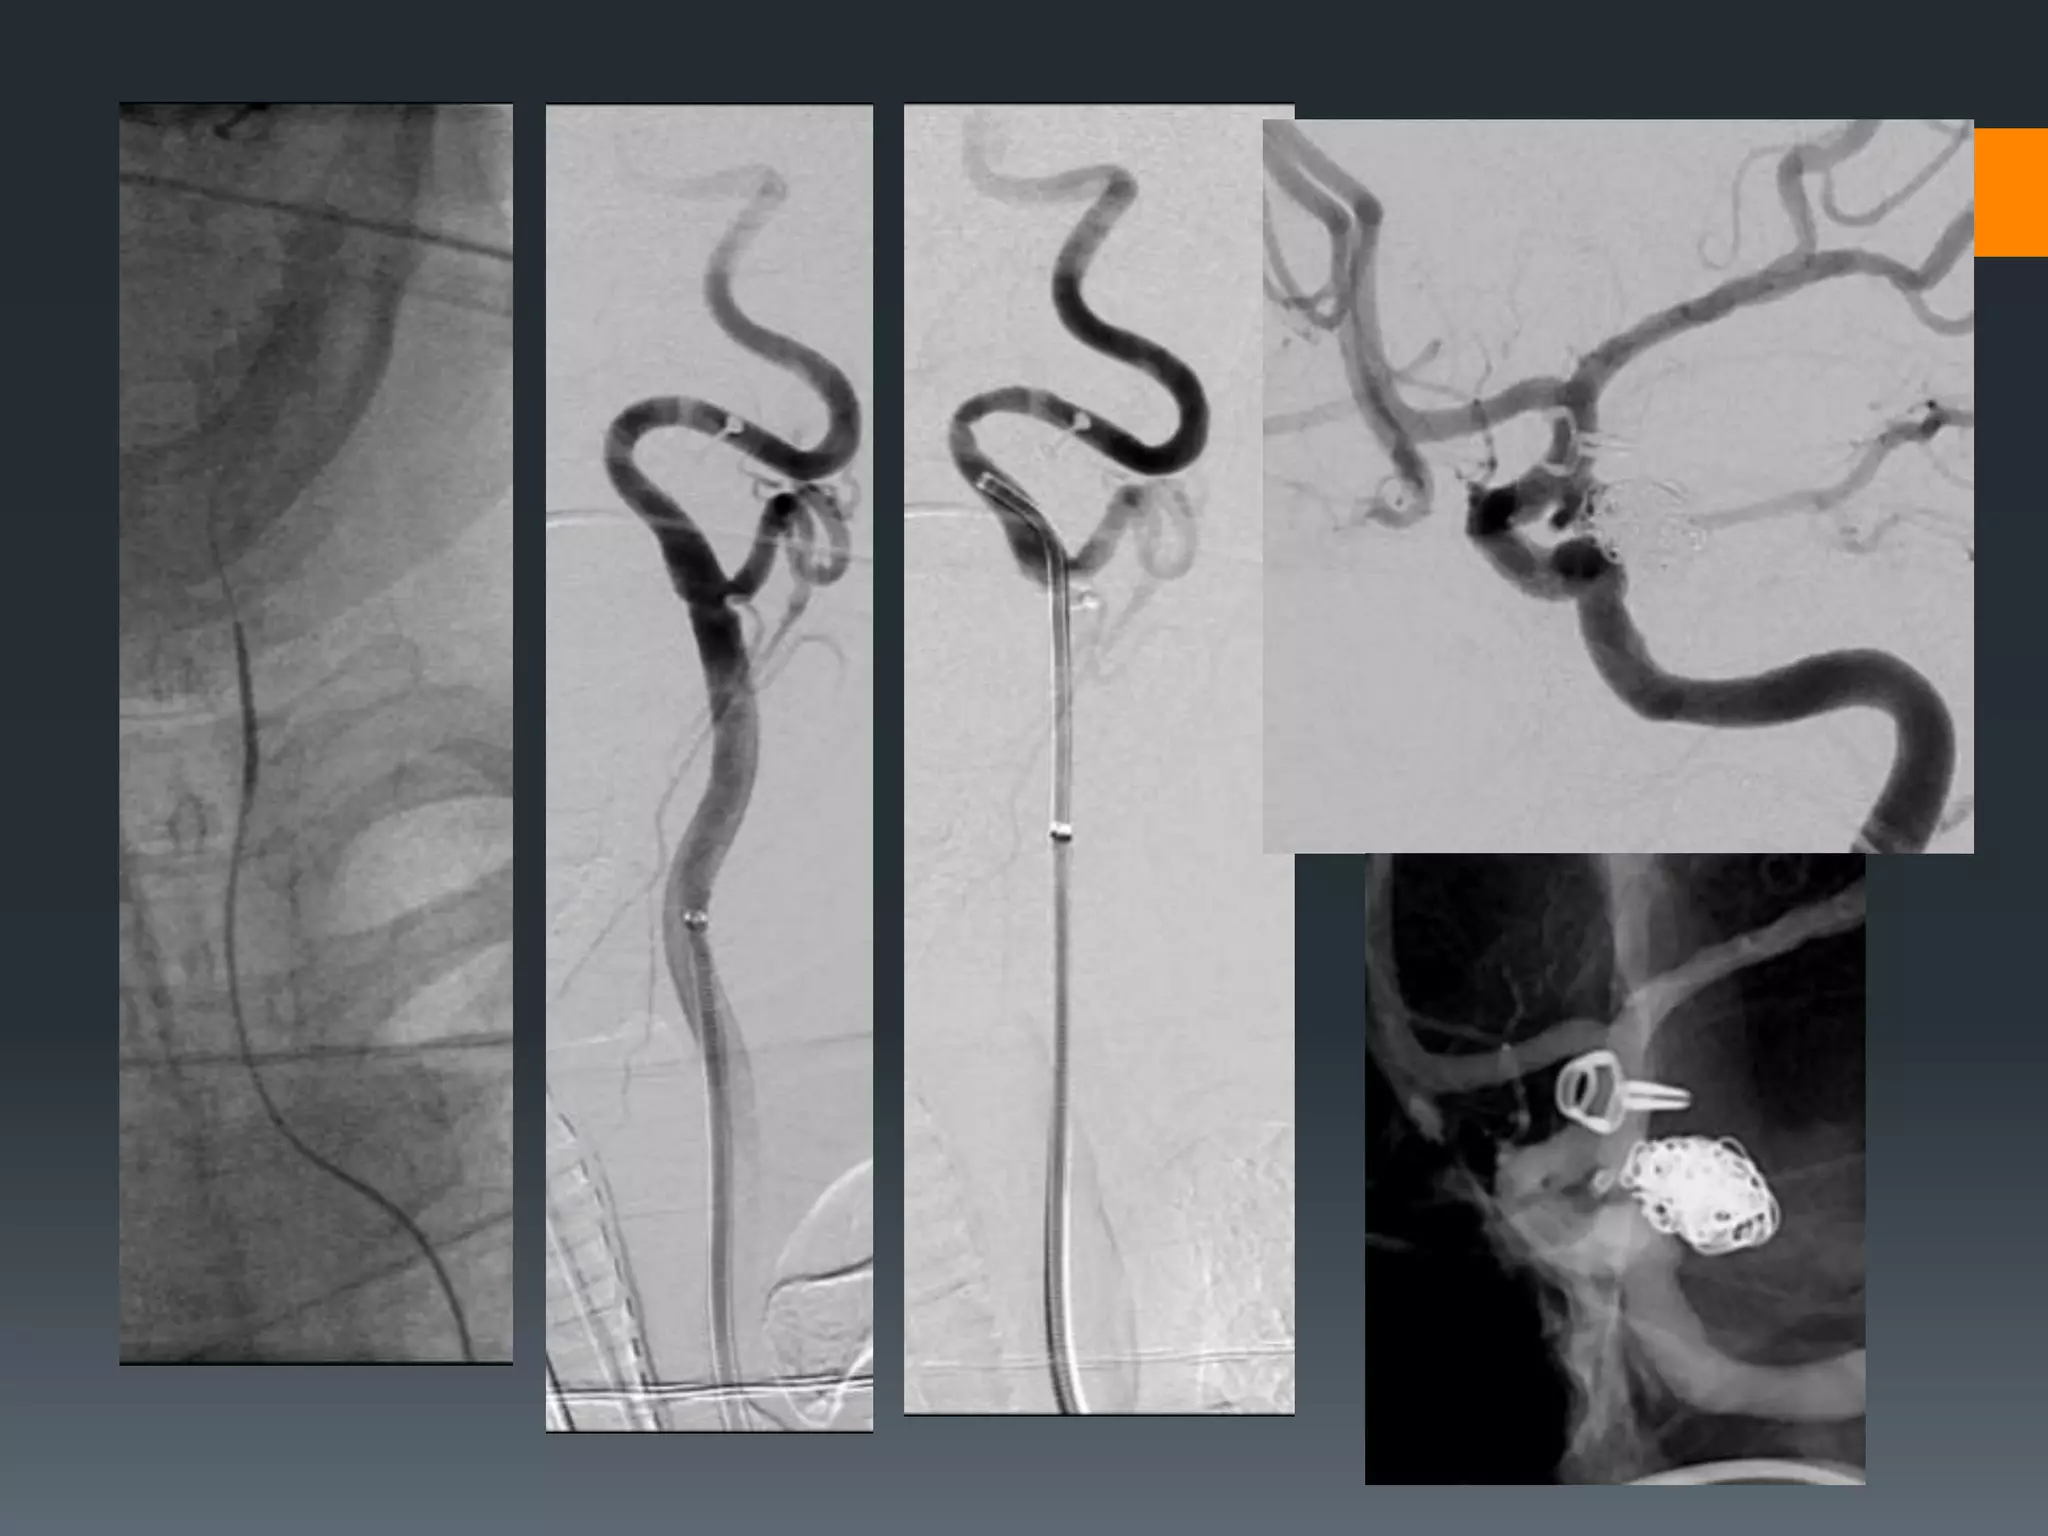

This document discusses tricks and techniques for difficult cannulations during neurointerventional procedures. It outlines strategies for accessing the aortic arch, internal carotid artery (ICA), and areas distal to aneurysms. Long sheaths, distal access catheters, and co-axial techniques are presented as options that have improved cannulation success. Guidance on sheath and catheter selection is provided for different vessel paths. The importance of catheter placement as high as possible in the ICA is emphasized. Reverse curve cannulations are also mentioned. Overall, the document stresses that careful cannulation is critical for procedural success and different strategies may be needed depending on the vessel target.